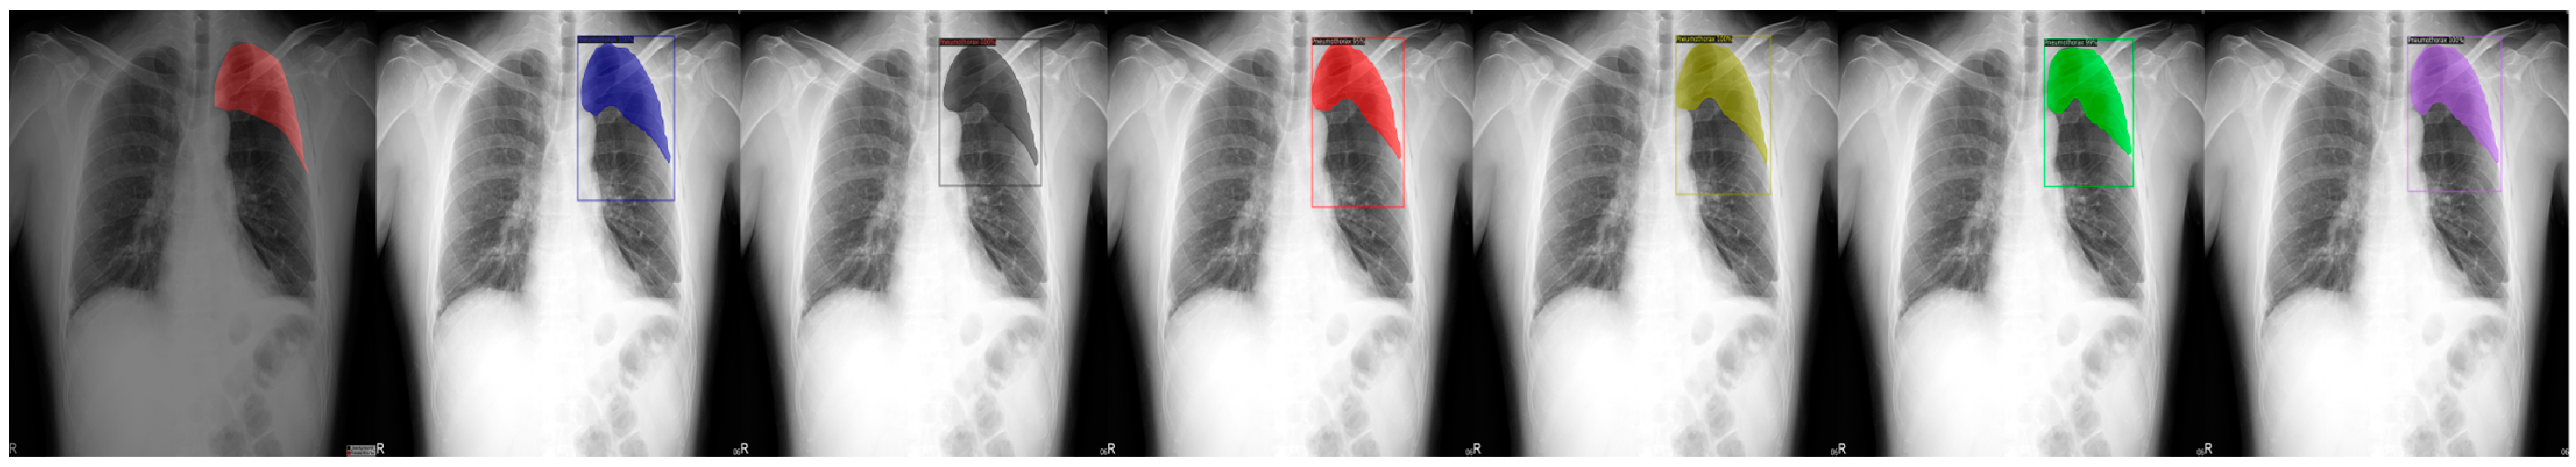

Figure 4.

From left to right: Ground Truth, ResNet50 (COCO), ResNet101 (COCO), ResNeXt101 (COCO), ResNet50 (LVIS), ResNet101 (LVIS), and ResNeXt101 (LVIS). This patient had pneumothorax in their top-left chest.

We chose a few examples to demonstrate the capabilities of various models. These images consisted of X-ray images of pneumothorax patients with different areas of disease inflicted. The inclusion of multiple positions and areas in the figures lets us observe the possible outcomes and the differences between the models. In Figure 3 and Figure 6, the patients had pneumothorax on the right side of their chest, with the patient in Figure 6 only affecting the top part, while the patient in Figure 3 had pneumothorax on the outside wall of their right lung. In Figure 4, Figure 5 and Figure 7, the patients had pneumothorax in the left side of their chest, while the patients in Figure 4 and Figure 5 had the upper part of their left lung mostly collapsed, indicating a serious issue of pneumothorax disease. In Figure 5, there are cavity areas at the bottom part, too. In the same image, the ground truth included a portion protruding below the area of the top detection portion due to the late-stage pneumothorax with most of the upper part of the lung collapsing, and all models were unable to detect the cavity of the protruded part. In Figure 7, the patient is seen with a fixation, with the pneumothorax affecting the top left lung, albeit with a smaller area.